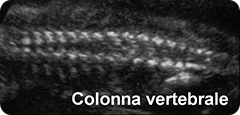

colonna vertebrale: valutazione della sua integrità